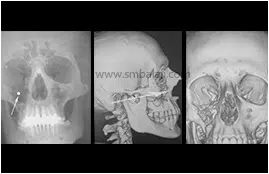

Eminent Facio-Maxillofacial Surgeon Dr. S.M. Balaji carefully analyzed the ballistics injury. A CT scan was taken to gauge the extent of complexity. The bullet had damaged the soft tissue and bone of the upper jaw including the floor of the eye socket as well as parts of the lower eyelid.

A diligent and intricate surgical procedure was performed by the surgical team headed by Dr. Balaji to restore normal function and appearance. The right eyeball was lifted and a Titanium mesh was placed to reconstruct the floor of the right eye socket. A bone graft was taken from the patient’s ribs and was used to accurately re-contour the smashed right cheek and eye bone. Hassanain’s facial appearance and eyesight were restored to normalcy, thanks to the accomplished efforts of Dr. Balaji and his team. A much delighted Hassanain and his family returned to Iraq.